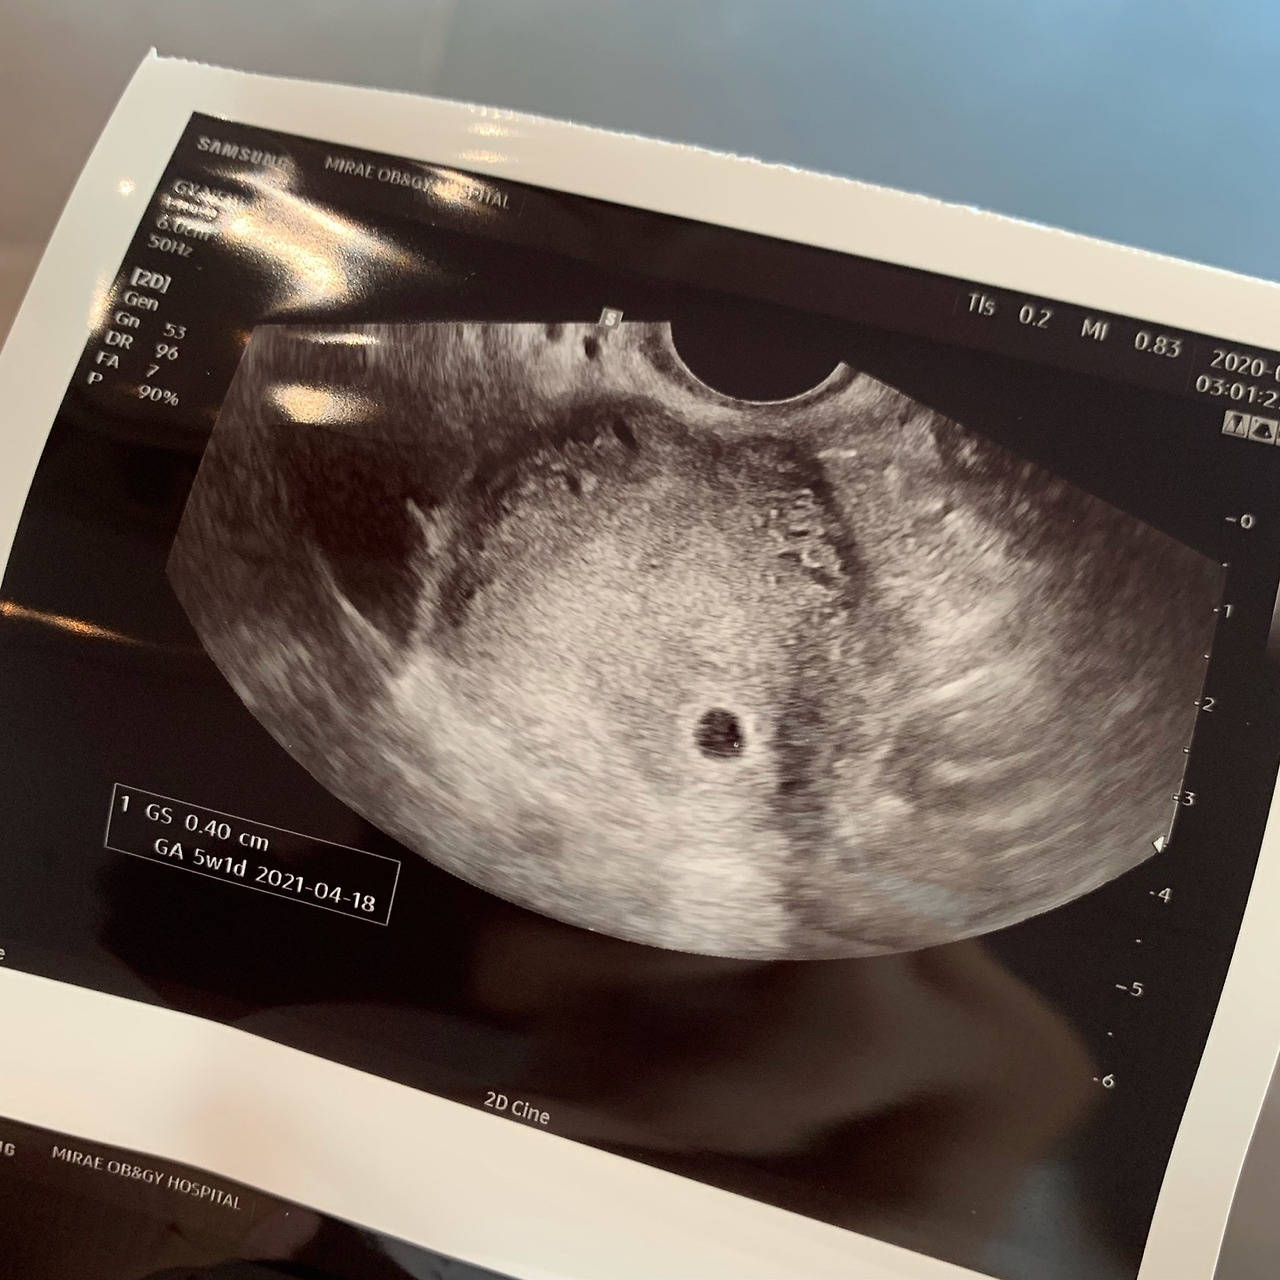

HCG 호르몬 수치가 9가 나오고 이틀 후 병원을 다시 찾았을 때 의사 선생님은 다시 한번 35라는 낮은 숫자를 주셨다. 아기집을 보기위해서 일주일 후 찾아오라고 했으나, 나는 임신을 미리 경험한 선배언니들의 조언에 따라 며칠의 시간이 더 지난 후에 아기를 낳을 수 있는 큰 병원에 가기로 했다.

그리고 그렇게 임테기가 더 진해질 수 없을 만큼 진해졌을 때,

나는 작은 아기집도 만날 수 있었다.